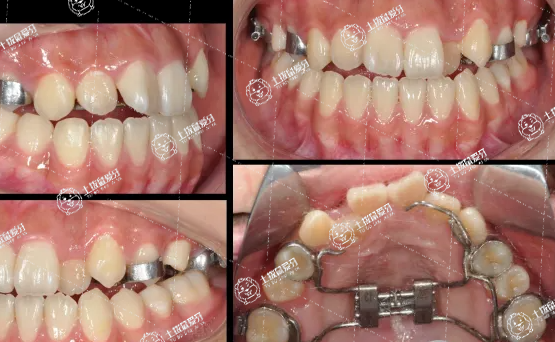

擴弓就是把牙弓擴大,擴弓的目的是為了獲得牙齒矯正時需要的間隙,一般是擴大上下合牙弓的寬度和長度。

通過正畸進行擴弓,主要是使兩側(cè)后牙向頰側(cè)移動而擴大牙弓,每側(cè)可得到1-2mm的間隙,利用這個間隙就可以使牙齒移動到正確的位置上,完成牙齒矯正。

擴弓會導致臉型變大嗎?盡管牙弓變寬了,但擴展的僅僅為毫米的距離,所以,在整體上并不會改變臉的寬度。

而且,深入來說,人的臉型主要由腭骨和下頜骨構(gòu)成,再加上面部肌肉,而擴弓也并沒有擴大頜面所有骨頭的寬度。因此,完全不用擔心臉會因為牙齒矯正擴弓而變寬變大!